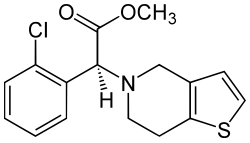

Inhibiting the formation of further blood clots, thrombosis prophylaxis, is the second important pillar of FATE treatment. It should be carried out as early as possible.[32] For this purpose, agents to inhibit hemostasis such as low-molecular-weight heparins are used first, along with agents to prevent platelet aggregation (thrombocyte aggregation) such as aspirin and clopidogrel.[39] For long-term prophylaxis, clopidogrel is preferably administered because it significantly prolongs survival compared with aspirin.[33][40] The use of the active ingredient rivaroxaban as another effective drug is also being discussed.[41] A 2021 study was able to show that the combination of clopidogrel and rivaroxaban is an effective recurrence prophylaxis.[42]